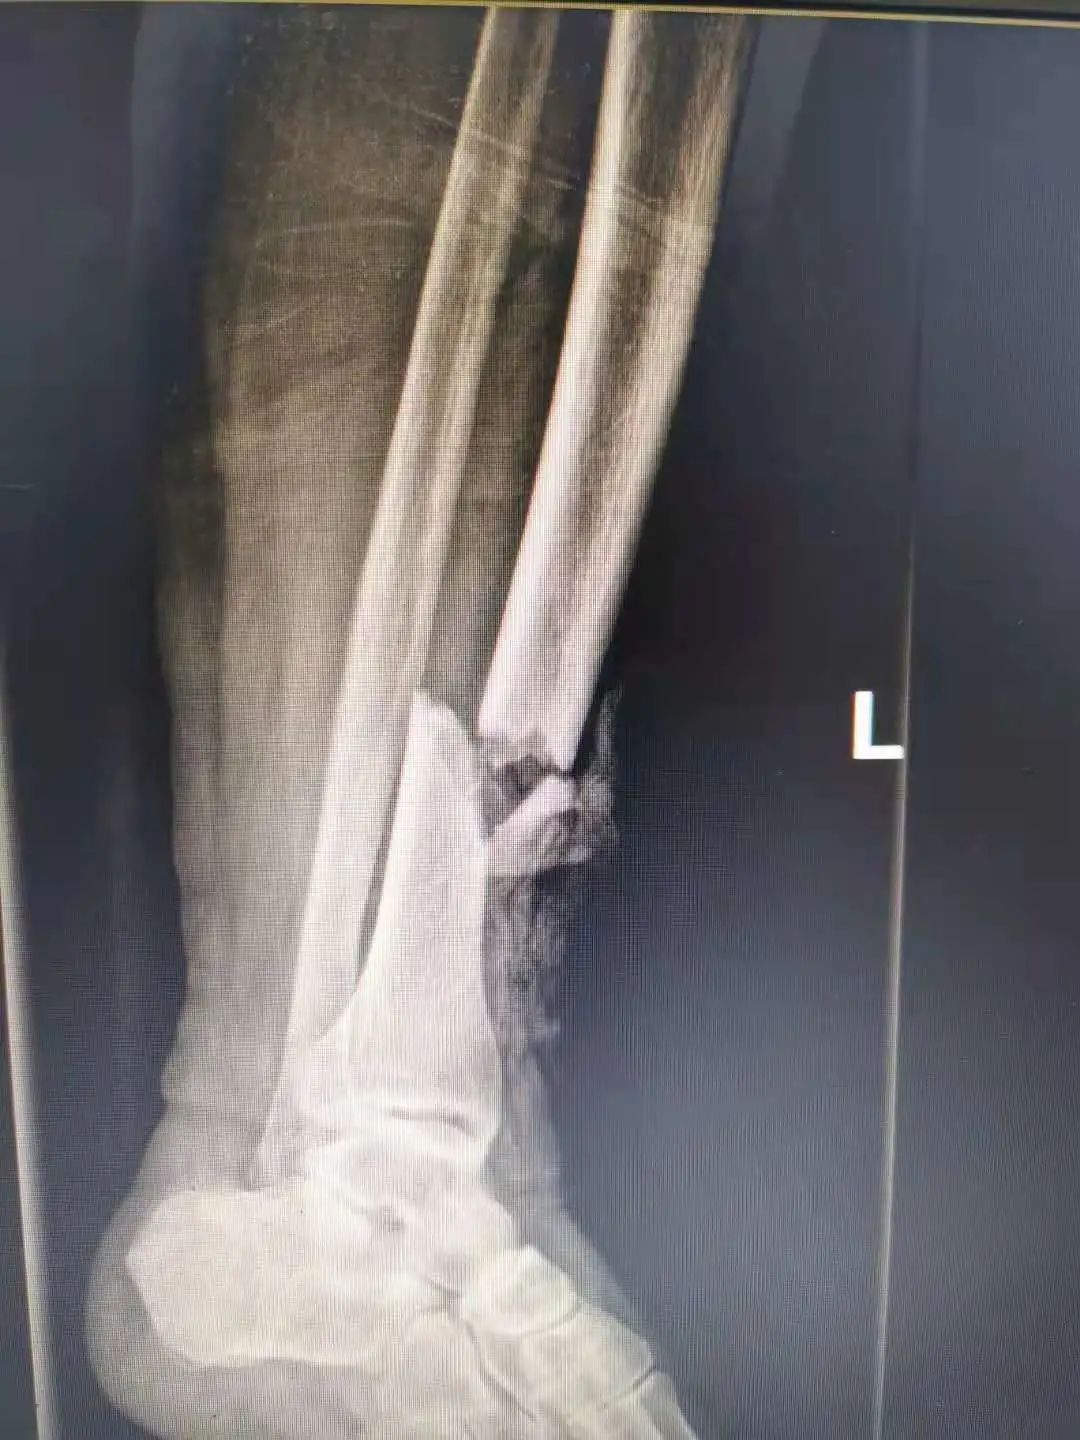

患者吕女士,66岁,因车祸受伤被送到我院急诊科,入院时左小腿上有一个镰刀型的伤口,长约15厘米,血肉模糊,经检查发现患者小腿前群肌肉挫裂严重,左胫骨开放粉碎骨折,骨质外露,创面及骨髓腔内大量泥土、布丝等污染物,急诊科完善相关检查后将患者送至骨科一区进行进一步治

疗。